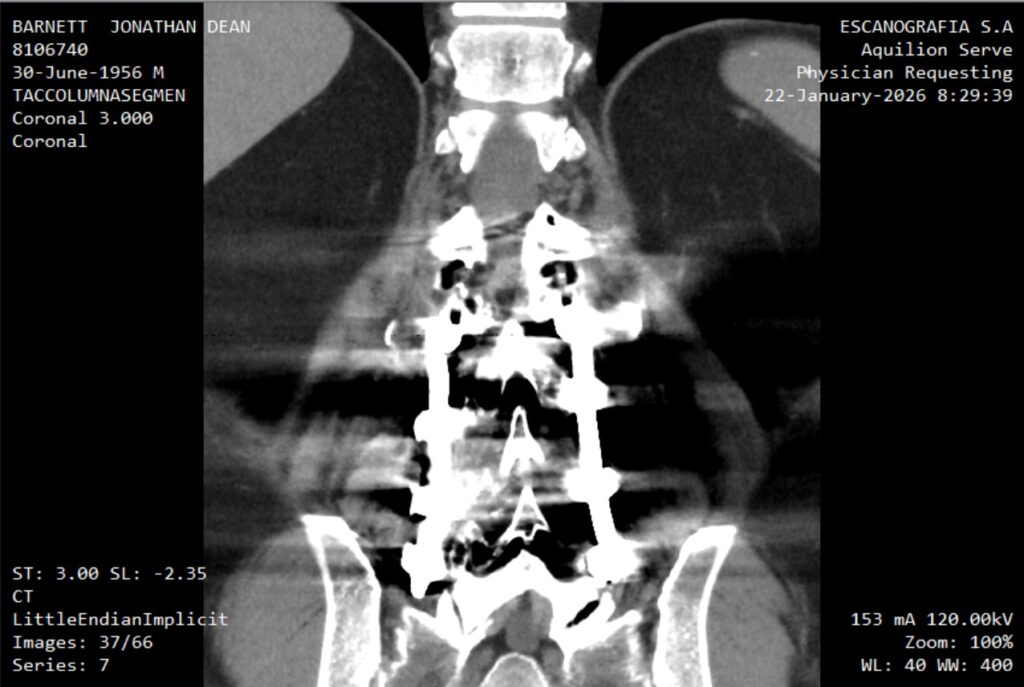

“…incipient degenerative arthritic changes in the right hip.” Not yet severe, but present and obvious.

But the physical exam by the Physiatrist who would actually perform a guided steroid injection, complicates that certainty. The source of the pain is not so obvious. The doctor’s probing fingers trigger pain into the back of my calf—classic nerve territory—almost as reliably as the pain I’ve been referring to as “hip pain.” Pressing on my spine itself doesn’t deliver the dramatic stabbing pain my mind expects. He picks up my right leg and moves it freely like a wooden marionette and I can only acknowledge honestly: no, that doesn’t really hurt, and he knowingly, but kindly, nods at my confession. So now I’m suspended between hypotheses: arthritis, sciatica, both, neither.

After my left hip replacement in August 2017 (another long and confusticating story), walking wasn’t just exercise. It was reclaimed territory. Independence. Sanity. Proof that I still belonged to my own body. Then came the spinal fusion in June 2023. Another negotiation. Another “you can have function, but you’re going to pay attention now.” Then the coclear implant in my skull, just weeks before leaving the USA for good.

That squiggly thing is an embolisation coil in the main artery to my testicles, but that’s another story for another time.

Soy bionico.

At this moment I’m waiting on a CT report. After waiting for an MRI. After waiting for an x-ray. Because medical care here is not unlike the medical care I left behind. We have to rule out the least invasive, costly, problematic solutions before we can consider the most extreme, which in this case isn’t really so extreme. Now we’re waiting on clarity. Waiting for someone to point to the map that is also my body and say: here.